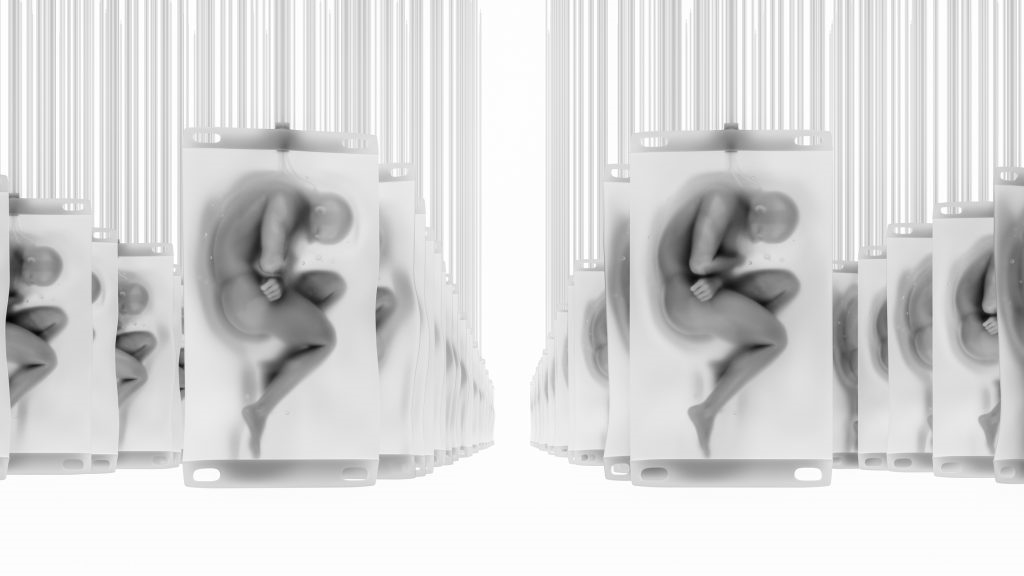

A projekt alapvető célja, hogy alternatívát kínáljon a hagyományos állatkísérletek mellett, és potenciális forrást teremtsen a szervátültetések számára. A tervezett technológia össejteket és génmódosítást ötvözve embriószerű entitásokat hozna létre, amelyekből az agyfejlődést gátló beavatkozások miatt csupán szervek fejlődnének ki. Ez elméletileg megoldást jelenthetne a világszerte súlyos szervhiányra, és csökkenthetné az illegális szervkereskedelmet.

Azonban a kezdeményezéssel kapcsolatban komoly etikai kérdések merültek fel. Egyes információk szerint a kutatók hosszú távon ennél is radikálisabb célt tűztek maguk elé: teljes, funkcionális emberi testek létrehozását agy nélkül, amelyekbe később agyátültetéseket lehetne végrehajtani. Bár a vállalat hivatalosan nem erősítette meg ezeket a spekulációkat, kijelentették, hogy fenntartják a jogot a témával kapcsolatos elméleti megbeszélések folytatására.